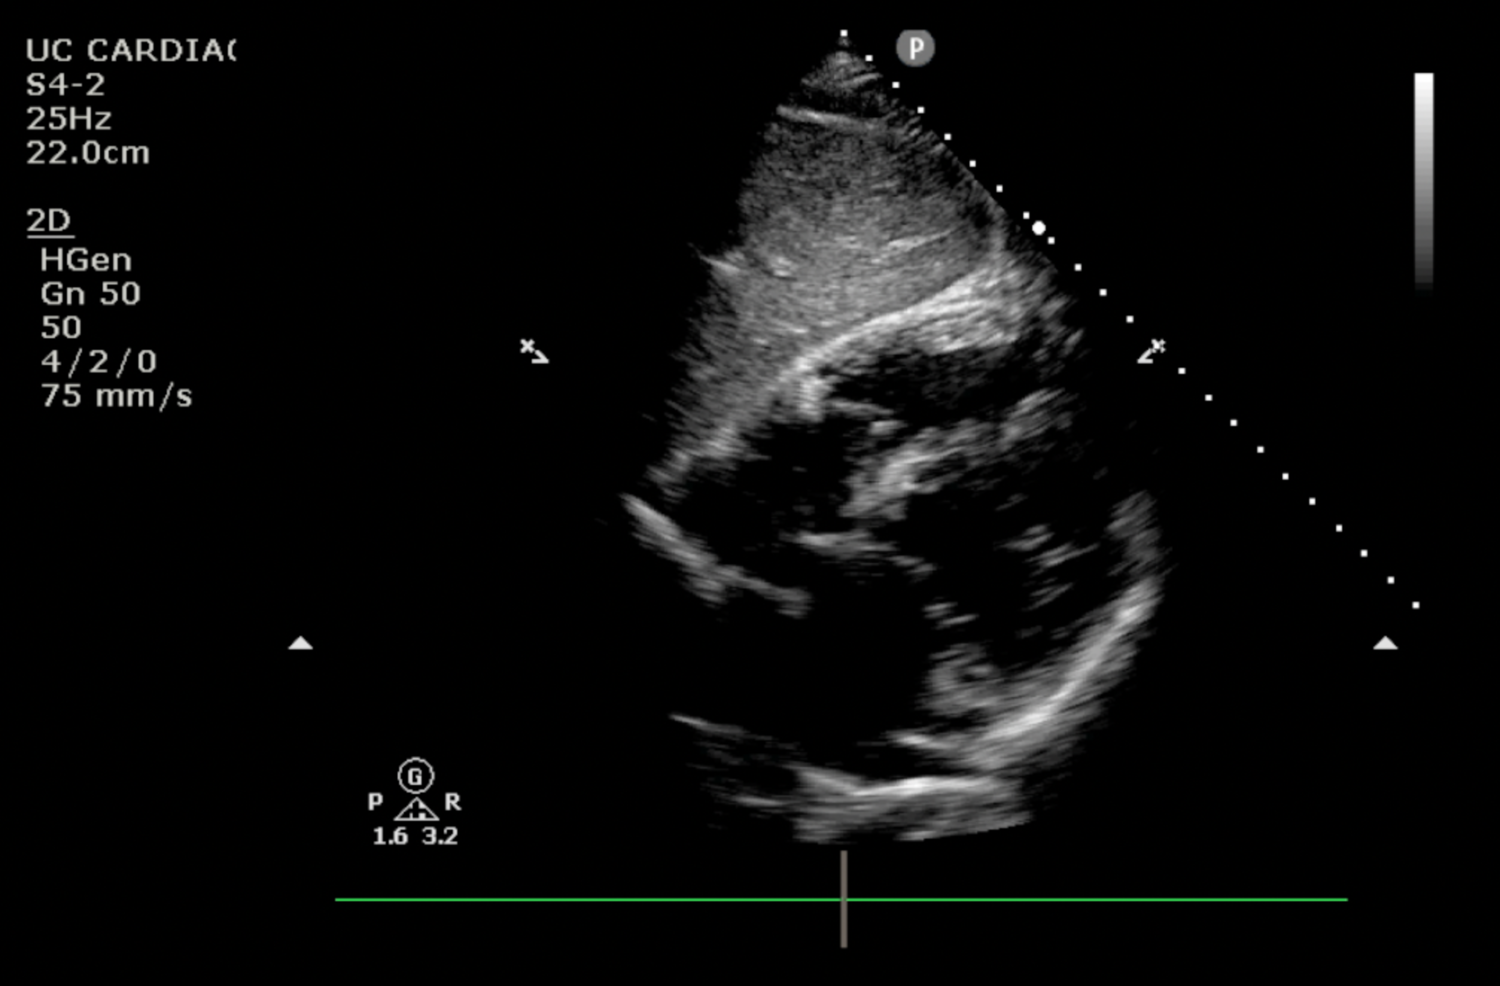

Sub-Costal view static image without pericardial effusion